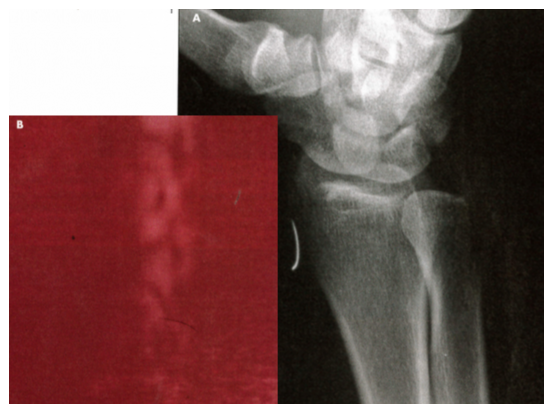

Foreign Body

04/30/2011

Rahul Gupta; Seema Gupta

A 40-year-old man presented to the emergency department with moderate to severe pain over the left lateral wrist. Earlier in the day, an iron rod had accidentally struck his...